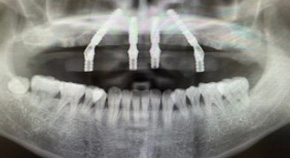

CTで確認すると骨量が充分にあるのですが細くて短いインプラントが7本入っている状態でした。オールオン4治療には必須の角度補正のSRAアバットメント(別名マルチユニットアバットメント)も装着されていない状態で偽物オールオン4というよりもオールオン7です。被せものはわずか3年で真っ二つに割れてしまったとのこと。下の歯の治療も放置されていました。

インプラント埋入後のレントゲン画像